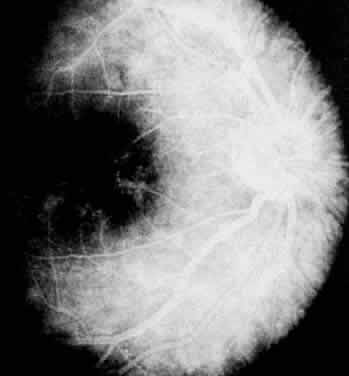

FLUORESCEIN ANGIOGRAPHY AND VITREOUS FLUOROPHOTOMETRY

In pars planitis, fluorescein angiography shows diffuse leakage from the retinal venules and capillaries, without any predilection for the inferior retinal vasculature (Figs. 5 and 6).28 Similarly, vitreous fluorophotometry in patients with pars planitis also shows no predilection for vascular leakage in the inferior peripheral retina.29 These findings suggest that snowbank is most likely a sequela from ocular inflammation, that inferior peripheral retina periphery is not the source of inflammation in pars planitis, and that pars planitis is not a localized inflammatory response of the inferior retina.

Fig. 5. Pars planitis. Fluorescein angiogram showing diffuse venous and capillary leakage.

Fig. 6. Pars planitis. Fluorescein angiogram of pars plana membrane showing diffuse leakage indicating neovascularization.